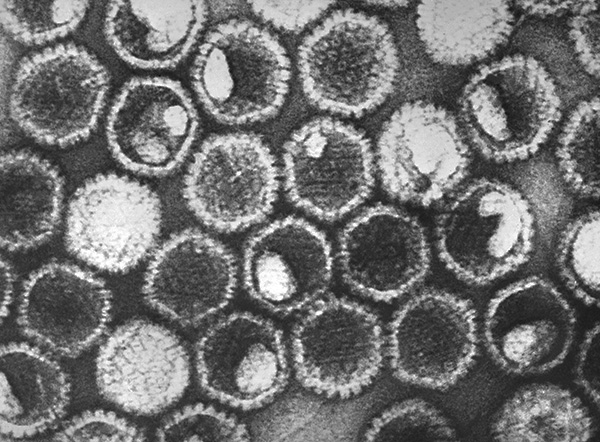

А здесь — фотография вирионов HSV-1 под микроскопом: